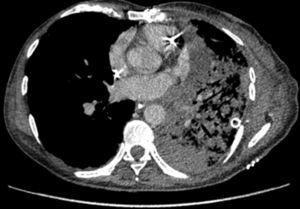

Suture dehiscence is usually an early complication and results in air leakage through chest drains or in pneumothorax and subcutaneous emphysema when drains have already been removed. It is due to poor healing (remember bronchial vasculature is sectioned during surgery), particularly when an associated infection is present. Diagnosis is based on bronchoscopy, although multisection CT is also very useful and provides 2D and 3D reconstructions. For small dehiscences (smaller than 1 cm), therapy can be conservative, with chest drains being left in place and aspiration bronchoscopies being performed, along with appropriate antibiotic and antifungal therapy when needed. Repeated bronchoscopies allow not only clear airways to be maintained but also the healing course to be monitored. For major or very early fistulas after surgery, surgical repair is recommended, using a repeated bronchial suture and a plasty based on adjacent well-vascularized tissue. When a poor condition of donor bronchial tissue is present, and in patients receiving double-lung grafts, right upper lobectomy followed by reanastomosis of donor's intermediate bronchus to receptor's main right bronchus is also possible. In left side transplantation, a longer bronchus usually allows bronchial tissue to be sectioned more proximally in a region showing a better condition 3.

Figure 1. CT image showing a bronchial dehiscence in posterior aspect of a left bronchial suture after double-lung transplantation.